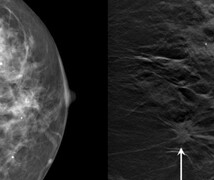

La mamografía tridimensional, también conocida como tomosíntesis mamaria, es una forma de mamografía digital. A diferencia de las mamografías digitales estándar, que crean una vista bidimensional desde la parte superior y los lados del tejido mamario, las mamografías con tomosíntesis en 3D toman imágenes de baja dosis desde diversos ángulos, usando principalmente la misma dosis de radiación que las mamografías habituales en 2D. Luego, una computadora reconstruye esas imágenes en una imagen en 3D del seno.

Las investigaciones indican que las mamografías en 3D detectan entre un 25% y un 35% más de cánceres de mama y producen hasta un 30% menos de resultados con falsos positivos. Los datos también muestran que la mamografía en 3D es más eficaz para detectar el cáncer de mama en tejidos densos. Todos los centros de Duke en los condados de Durham, Orange y Wake ofrecen tomosíntesis en 3D para todas las mamografías de detección y diagnóstico.